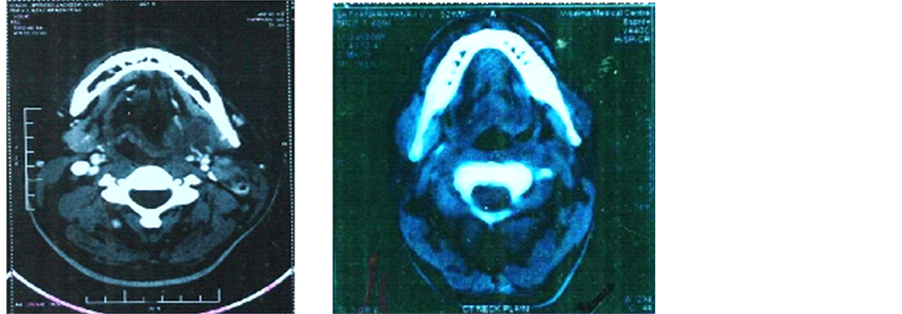

Pre treatment Post 1 year after treatment

Figure 2. (a) Pretreatment―CECT of neck showing an oropharyngeal growth involving the right base of tongue; (b) Post treatment―CECT of neck showing small residual thickness in the right oropharyngeal region.

Figure 3. (a) Pre-treatment CT scan showing a mass measuring 3.6 cm × 2.5 cm × 2.0 cm on the right lateral oropharyngeal wall; (b) Post-treatment CT scan showing reduction in the size of submandibular lymph node to 0.5 × 0.5 cm.